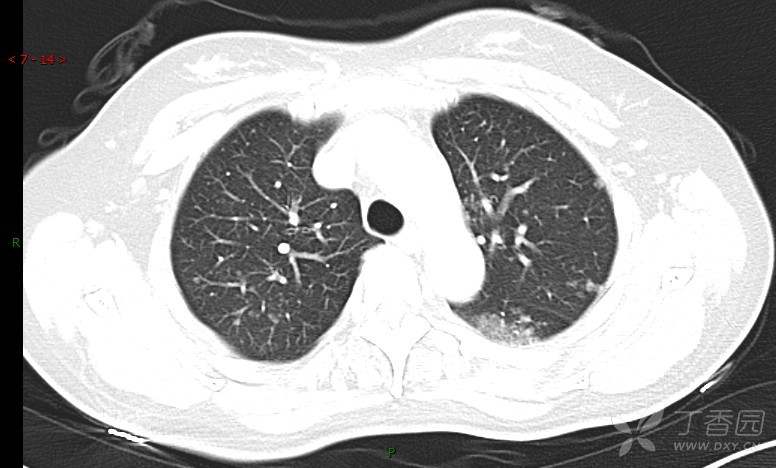

腺泡结节影,蜂窝征,这些都在提示……(病例3连发,附其他2例链接,病理已公布)

咳嗽1年余,加重7天。

患者于1年余前始受凉后出现咳嗽,多为干咳,未在意,未到医院就诊。近3月患者出现咳痰,多为黄色粘痰,量大,伴乏力,偶有头晕、心慌,无发热、胸痛、憋喘,无低热、盗汗、咯血、胸痛,无头痛,无恶心、呕吐、腹痛、腹泻,无尿频、尿急、尿痛,在当地诊所给予抗感染等对症支持治疗(具体药物及剂量不详),症状仍时有反复。患者于1月余前到外院就诊,行胸部CT提示双肺炎症,左肺重,考虑为“间质性肺炎”,给予“左氧氟沙星、利巴韦林、头孢哌酮舒巴坦钠注射液”治疗,复查胸部CT示病灶吸收不理想,后出院继续于诊所对症治疗(具体药物及剂量不详),效果欠佳。7天前患者无明显诱因出现上述症状加重,为求进一步诊治,特来我院就诊,我院门诊以“肺炎(重症)?”收入留观室,留观室给予“盐酸莫西沙星氯化钠”等对症治疗后,今日转入我科。患者自发病以来,神志清,精神差,饮食正常,睡眠增多,大小便正常,体重近3月减轻5公斤余。